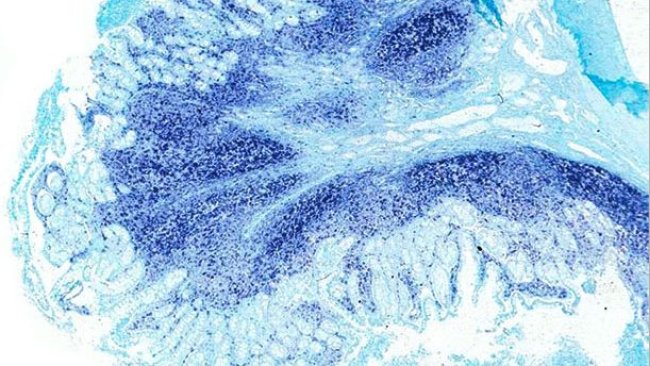

Zdjęcia najważniejszych chorób świń

Choroby układu pokarmowego świń, które wcześniej były traktowane indywidualnie, ukierunkowane na pojedynczy patogen, obecnie tworzą zespół chorób układu pokarmowego, z którym musimy zmierzyć się z różnych perspektyw.

Ostatnio wskazywano PCV2 jako czynnik etiologiczny biegunki u świń, i proponowano jelitową postać cirkowirozy (PCV2-ED) jako jedną z form choroby związanej z PCV2 (PCVD)